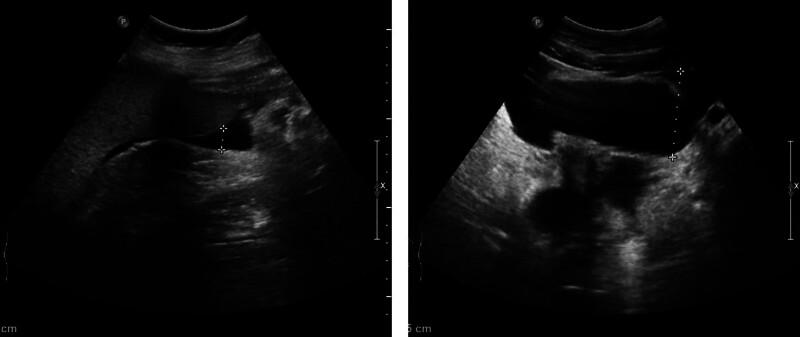

We herein report a case of a 29-year-old woman who presented with abdominal pain, nausea, and vomiting, with no history of adverse reactions to any allergens. Laboratory test results revealed a normal count of peripheral blood eosinophils. Ultrasound and computed tomography revealed thickened intestinal walls and ascites in both the abdominal cavity and the pelvic cavity. Multiple endoscopic biopsies targeting several swelling segments of the intestinal wall revealed no increase in the number of eosinophils.

Symptoms improved rapidly, and the thickened intestinal walls returned to a typical level.

我们在此报告一例29岁女性患者,她出现腹痛、恶心和呕吐症状,既往无任何过敏原不良反应史。实验室检查结果显示外周血嗜酸性粒细胞计数正常。超声和计算机断层扫描显示肠壁增厚,腹腔和盆腔均有腹水。针对肠壁多个肿胀节段进行的多次内镜活检显示嗜酸性粒细胞数量未增加。

症状迅速改善,增厚的肠壁恢复到正常水平。